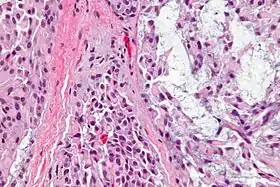

قد تكون الخلايا الظهارية العضلية مغزلية الشَّكْل، بلازماوية أو واضحة. يغيب وجود الأنابيب أو الخلايا الظهارية وقد توجد بنسبة صغيرة أقل من 5% كما هي مسمَّاه. الأورام الظهارية العضلية التي تحتوي على نسبة كبيرة من الأنابيب تصنف كأورام غديَّة متعددة الأشكال ( والتي يجب أن تحتوي على اللحمة الغضروفية المخاطية المميِزة للورم الغدي متعدد الأشكال، والتي لا تكون موجودة في الورم الظهاري العضلي ).